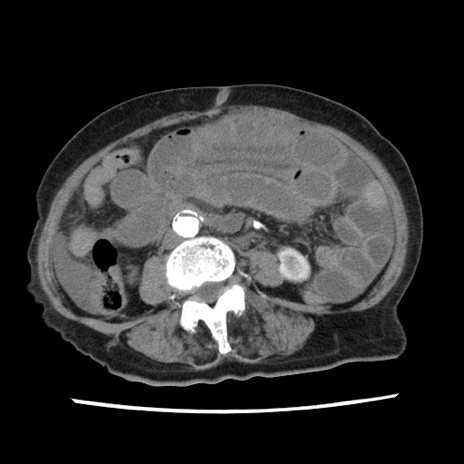

症例1(横断像)

【症例】80歳代女性

【主訴】腹痛

【現病歴】8時間前から腹痛あり来院。

【既往歴】糖尿病、脂質異常症、子宮体癌にて子宮全摘術

【身体所見】意識清明・会話良好だが腹痛で苦悶様、全腹部にわたって反跳痛と圧痛あり

【データ】WBC 13600、CRP 0.14、LDH 224、CK 90